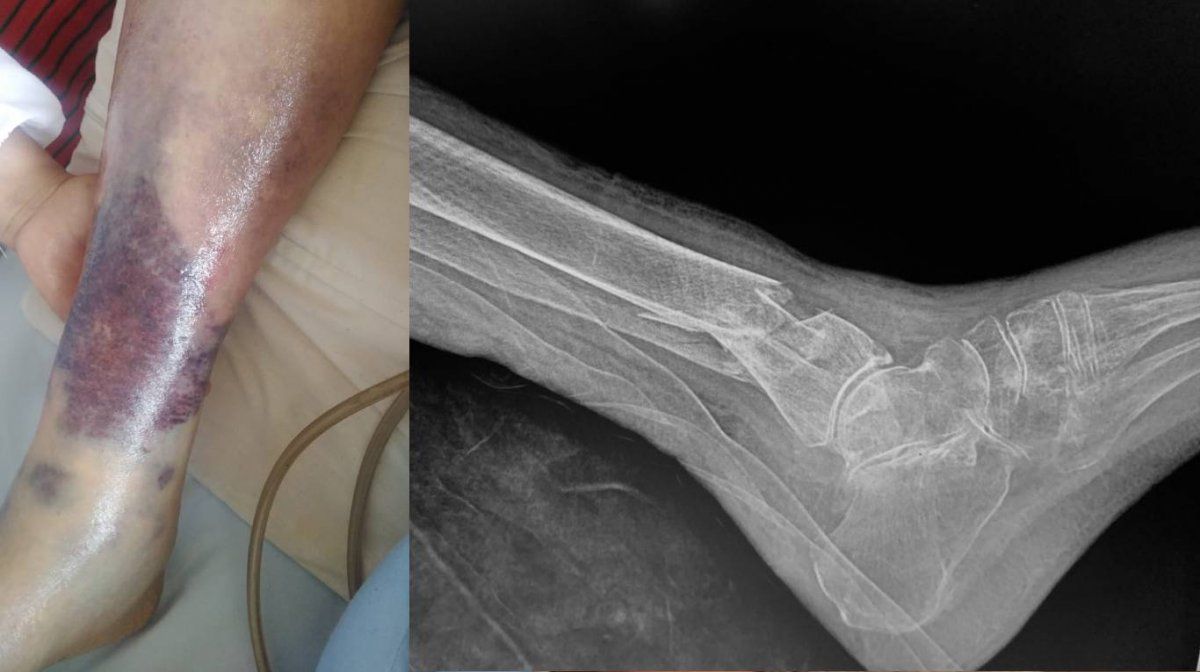

Eva Mange quedó a cargo de cuatro enfermeros mientras la villana de la telenovela "María Mercedes" iba a trabajar y todo fue un infierno. Le quebraron la tibia y el peroné y ahora está enyesada.

“¡La gente cada día está peor! Esto le hicieron a mi abuelita y ninguno de los cuatro enfermeros sabe qué pasó, mientras yo trabajaba. Los mexicanos pinches sin educación aunque presuman títulos de enfermeros. Asco de personas. #MéxicoDespierta #MalditosMilVeces”, escribió en Twitter.

En enero, la señora fue víctima del horror. Tanto la cantante como su hermana se hisoparon para ir a celebrar con ella sus 103 años y al llegar descubrieron una escena digna de una película de terror. Estaba toda lastimada y sin recibir atención médica.

“Estos son los cuidados que le han procurado. Tiene 9 escaras decúbito. No puedo creer que esto esté sucediendo. Situación que me ocultaron durante todo este tiempo. Hoy por fin pude ver todo el daño ocasionado. He tomado cartas en el asunto. Cárcel a los responsables. De repente piensas que un lugar donde hay personas con las que pueda interactuar es saludable, pero nos hemos dado cuenta que si hay gente mala que te toca, te desgracia la vida”, señaló Zapata en aquel entonces.